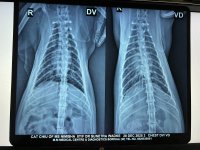

In early August, we got a repeat x-ray (attached) done which still showed bronchial lung pattern. She got Lasix and Penetrat (similar to Frenzyme). She stayed ok for about a month before symptoms returned.

In mid Sept, she again got an x-ray with bloodwork (both attached) and got prescribed Omnacortil (Prednisolone), Bioclan (Clindamycin Hydrochloride) and Fexorise (Fexofenadine Hydrochloride IP 120 mg). She was ok for nearly 1.5 months before the wheezing returned along with a sort of cough too.

Yesterday was the x-ray which still showed congestion. We did a 2d echo (scans attached). Vet said stuff like HCM, regurgitation, dilation. I had briefly read about HCM and got overwhelmed and didn't ask the vet for more details. But she sent me off with 30 days medicines (long list of meds below) and we'll do a repeat 2d echo after a month. ETA: she lost about 0.5 kg in the last 15 days.

4.2 Xray - DV VD - Chiu - 20Dec2025.jpeg2.4 MB · Views: 41 -